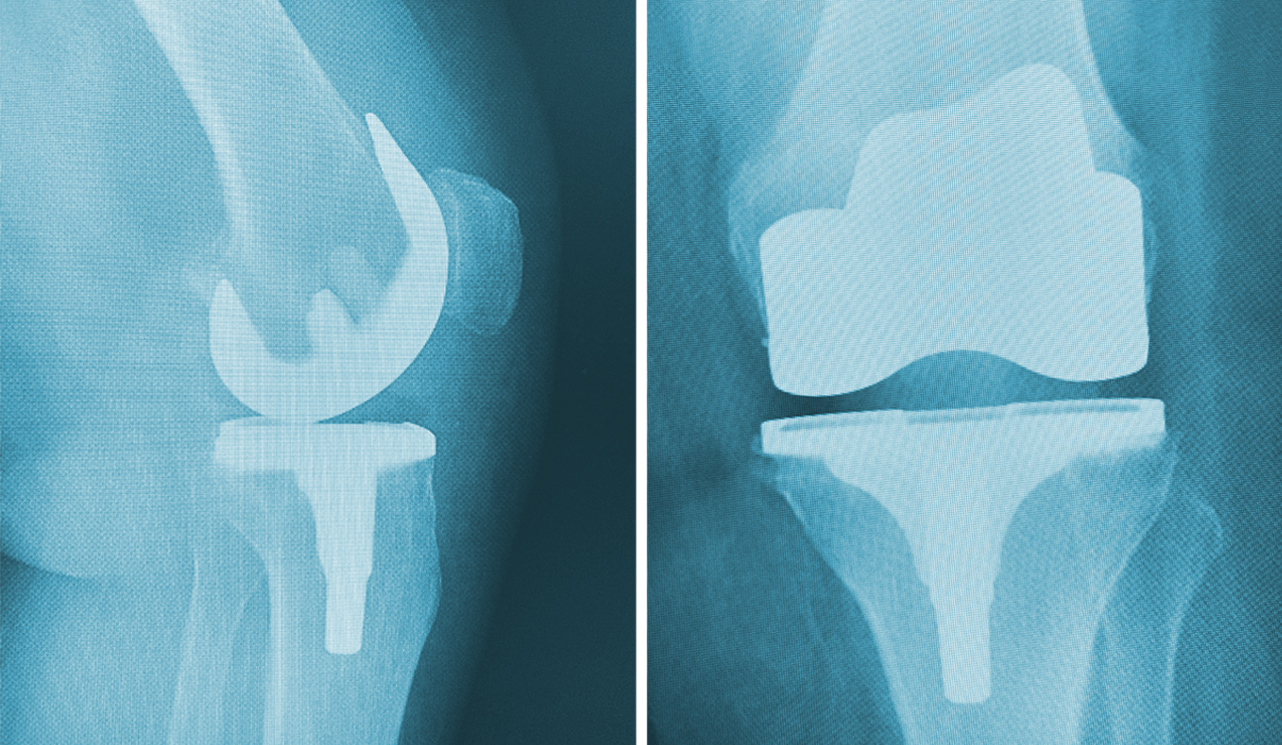

Diz ve Kalça Kireçlenmeleri Tedavisi